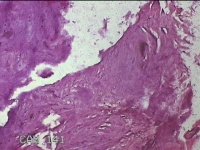

右侧中指指间关节背侧包块

性别

男

年龄

46岁

临床诊断

皮下结节

一般病史

发现右侧中指指间关节背侧一包块,伴间断性疼痛不适,考虑痛风结节。

标本名称

大体所见

灰白粉红色包块0.8x0.7x0.3cm一堆。

图1